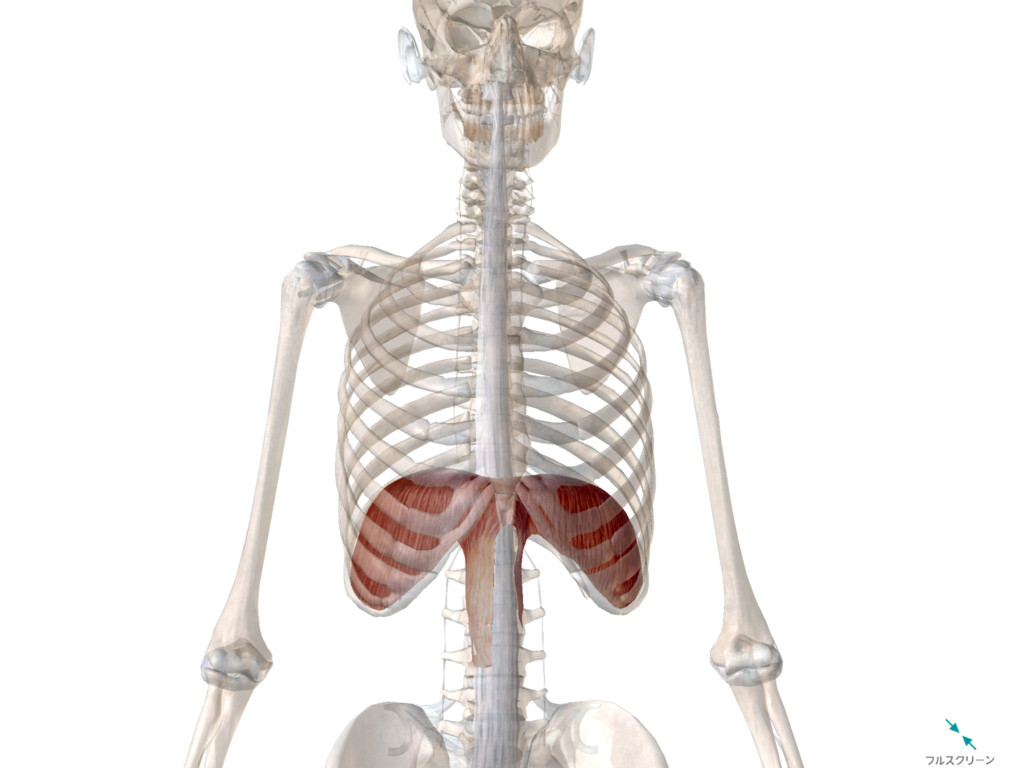

横隔膜はこちら

肺の真下にある、赤いやつが『横隔膜』ですね。

この東京ドームの屋根部分みたいなやつが、東京ドームの屋根がしぼむかのように下の方に下がっていくと、空気が入ります。